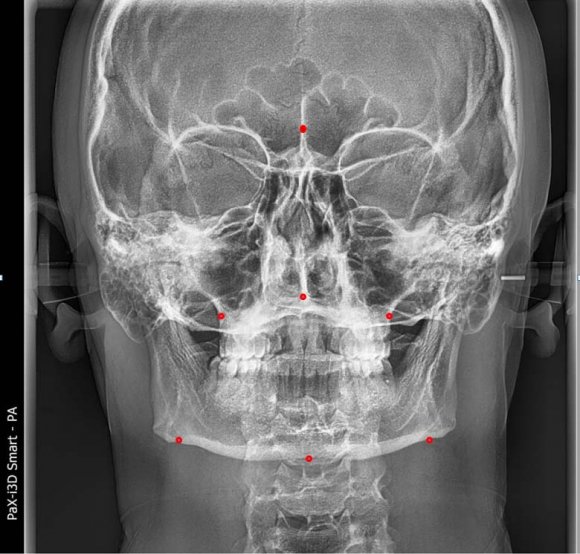

We described the comparison of the upper and lower jaws in such a perfect way that it is impossible not to use these indicators during this research. To determine the relationship of the upper and lower jaws to each other, a line is drawn from the Cg point to the J and Ag points on the right and left sides [9], the names of these points and lines are given in tables 1 and 2, and pictures 1 and 2. The right J and left J points are also connected, resulting in the formation of J-Cg-J triangle. Similarly, a horizontal line is drawn from the right Ag to the left Ag point and the triangle Ag-Cg-Ag is formed. These triangles are divided into two using MSR and four triangles: right J-Cg-MSR and left J-Cg-MSR; Ag-Cg-MSR and Ag-Cg-MSR are produced (Figure1). In this article, the authors compared the length of the sides of the triangles and evaluated their symmetry [6,9,10]. The indicators of the upper and lower jaw symmetry of representatives of the Uzbek population were determined, compared the indicators of men and women Grummons indicators (table 3). We compared the indicators of "comparison of the upper and lower jaws"of the representatives of the Uzbek population with normal physiologicalbite with the results of the average indicators of men and women. The J-MSR index for Uzbeks is 31.72±0.18 mm on the right and 31.69±0.17 mm on the left; in men, right 32.07±0.21mm. and left 31.96±0.21mm; right 31.25±0.25mm in women and left 31.33±0.27mm. equal to, and no significant difference was found when they were compared with each other or compared with the average values (P>0.05). Ag-MSR index in men is 42.6±0.25mm right and 42.49±0.29mm left; Ag-MSR index of women is 39.98±0.37mm right and 41.0±0.35mm left. is equal to It was found that the average of the Ag-MSR indicator of Uzbeks is equal to 41.49±0.25 mm on the right and 41.86±0.24 mm on the left. Now, when we compared Ag-MSR values of women and men with respect to mean Ag-MSR values, only female Ag-MSR R values were significantly different (P<0.05). When the Ag-MSR indicators of men and women were compared, it was found that there was a reliable difference between the Ag-MSR R indicator of men and the Ag-MSR R indicator of women (P<0.05). The average of the Cg-J indicator of Uzbeks is 68.82±0.47 mm on the right and 68.63±0.46 mm on the left. Cg-J index in men is 71.09±0.58mm right and 70.87±0.55mm left; in women, the right is 65.7±0.45mm and the left is 65.55±0.49mm. When comparing the Cg-J index of women and men, there are reliable differences in the Cg-J index of men compared to the Cg-J index of women (P<0.05). Now, when comparing the Cg-J index of women and men to the average of Uzbeks, a reliable difference was found only in men's Cg-J index compared to the average Cg-J index (P<0.05).

Figure 1: Points (Landmarks) used in Maxilla-Mandibular Relationship Indicators of the Frontal Cephalogram